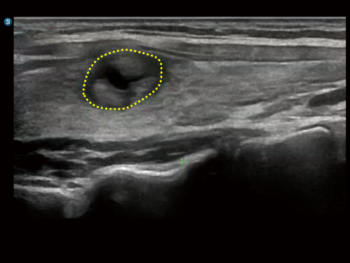

S-Thyroid

Цогц шийдэл бүхий дэвшилтэт хэрэгсэл бөгөөд ACR TI-RADS зааврын дагуу сэжигтэй бамбай булчирхайн бүтцийг илрүүлж, ангилахад тусалдаг. Энэ систем нь шарх болон зангилааны хил хязгаарыг автоматаар тодорхойлж, үзлэгийн дараах тайланг бэлтгэдэг.